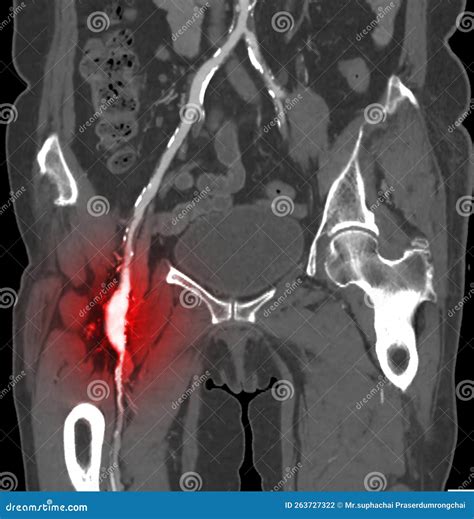

• Ischemic Symptoms: In rare cases, clots forming inside the aneurysm can break loose, traveling downstream to block blood flow, causing coldness or color changes in the lower leg.

Physicians use various imaging techniques to confirm the presence of a femoral artery aneurysm and assess its size, location, and potential for complications. Accurate diagnosis is vital for planning the appropriate treatment path.

CT Angiography (CTA) Provides highly detailed cross-sectional images to map the vascular anatomy and plan for potential surgery.